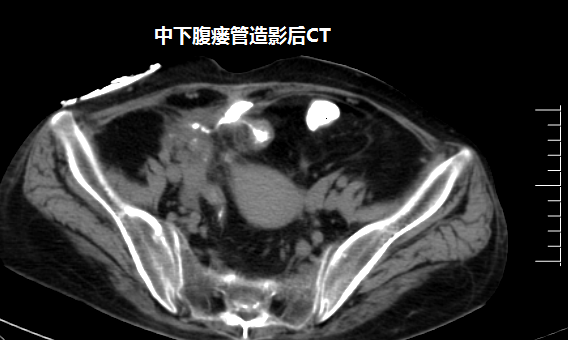

吴万庆副主任医师接诊后,详细了解病史及查体,经过造影及CT检查,确定瘘口的部位及腹腔脓腔情况,发现患者腹壁有三个瘘口,粪便外渗,诊断考虑为克罗恩病并发肠瘘。